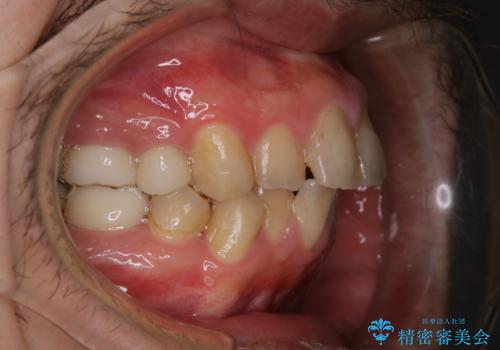

インビザライン矯正治療のスキャニング前のPMTC

- インビザラインでのスキャニング前にPMTCを希望されました。PMTC60分コースを行いました。

矯正治療前には、PMTCで歯石や汚れを取り除き、健康的な歯肉の状態にすることが大切です。PMTCでは、がたつきになどより、ご自身では取り切ることのできない細かい部分などに付着した汚れなども、専門的な機械や材料を使用してクリーニングを行います。